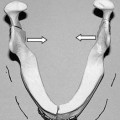

The fibula free flap has become the gold standard for reconstructive procedures of large mandibular defects owing to its excellent bone stock, skin paddle availability, sensory potential, and acceptance of osseointegrated implants. Initially described by Taylor, it was applied to the mandible and popularized by Hidalgo and others for head and neck reconstruction.161–165 The early application of the fibula osteocutaneous flap revealed a high failure of the cutaneous paddle due to variations in the septocutaneous and musculocutaneous perforators and the early loss of the skin paddle during mandibular reconstruction. The flap has since been introduced with a variety of modifications using osteotomies and sensory innervation and applied to numerous regions of the head and neck.90,165–169

Indications

The fibula free flap is most commonly used as an osteocutaneous free tissue transfer that is ideal for reconstructing oromandibular defects, although utility in the orbitomaxillary regions has also been successful. It is the flap of choice in composite segmental oromandibular defects of the anterolateral mandible with soft tissue loss when osseointegrated implants or sensory innervation would benefit the patient. It is also useful in reconstructing oromaxillary and orbitomaxillary defects, providing excellent bone stock, which permits osteotomies for accurate contouring and insetting170